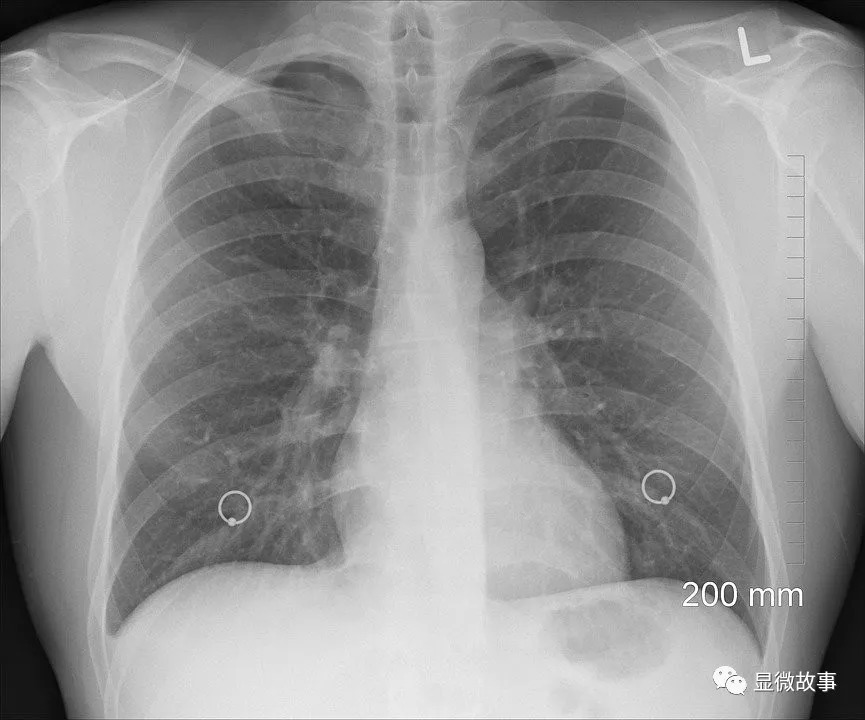

图 | 江华医生(右)和他的患者

图 | 江华医生(右二)和患者一家的合影